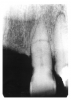

Figure 2 illustrates advanced enamel caries on the mesial surface of the premolar.

Figure 2 - Advanced Enamel Caries

Figure 2